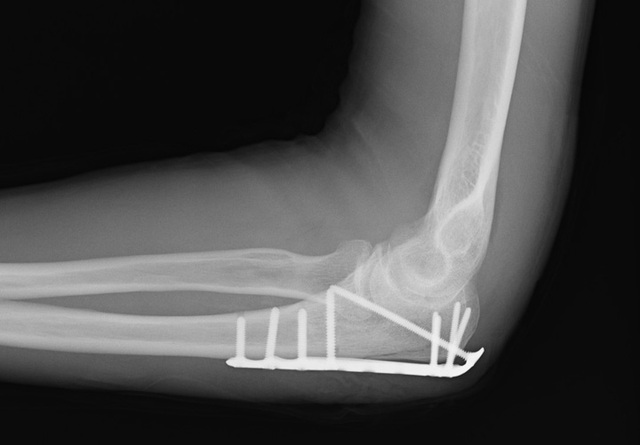

El 14 de mayo me había roto el brazo. Yo estaba en preescolar y cayó de las barras de mono. Era el día de la gradutation y al día siguiente me fui a la cirugía Emergancy. Los médicos dijeron que mi brazo nunca volvería a crecer y, finalmente, lo hizo crecer.